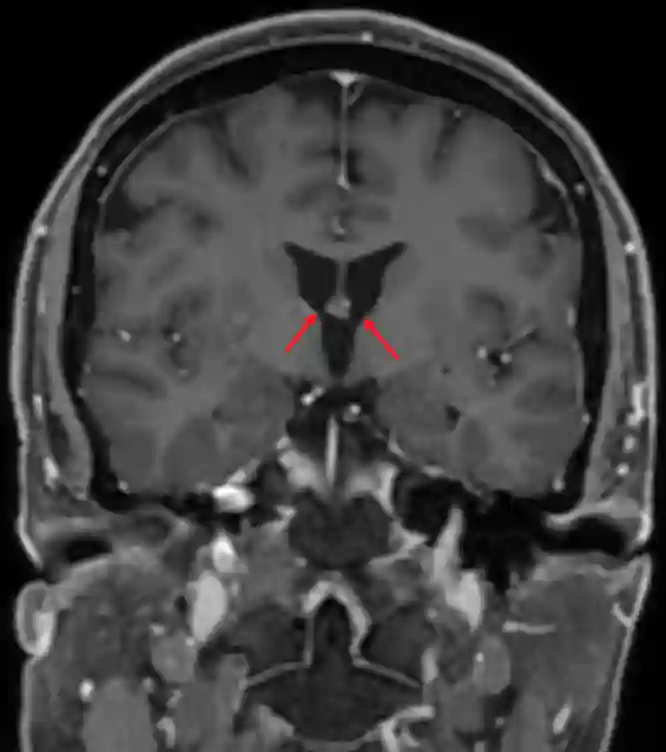

Foramen Monroi im MRI

Foramen Monroi im MRI (T1 mit Kontrastmittel coronal).